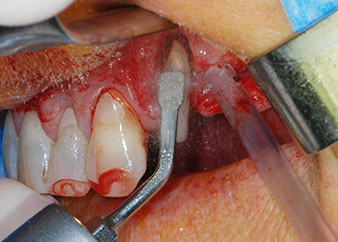

One month later, on the day of surgery, pain and inflammation at tooth 24 were minimal, but mobility of Miller class 2 was still present. After opening the flaps and cleaning the periapical and peri radicular infected tissue, the extent of the bone defect became obvious (Figs. 2 and 3).

At the buccal root, all vestibular and distal bone was missing. Attachment was essentially restricted to the palatal root, underlining the preliminary poor prognosis. Tooth 27 also showed a reduced horizontal attachment and a minimal apical rarefaction (cf. Fig. 1) without clinical symptoms.

However, we maintained our initial plan to retain both teeth as temporary bridge abutments during the six-months osseointegration period of the implants. At reentry, the situation would have to be reassessed. First, in an attempt to manage the endo-perio problem, the remaining root surface was carefully debrided with piezoelectric equipment (Piezomed, W&H, used with the spatula-shaped insert S1, originally designed for erosion of the lateral sinus wall) (Fig. 4).